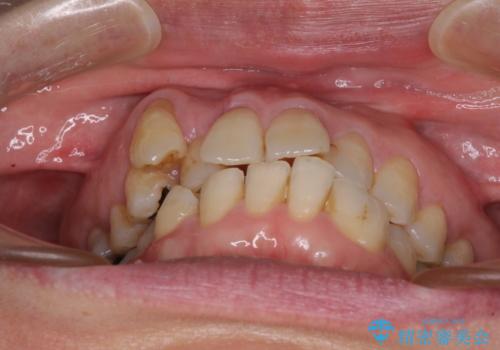

- 長年前歯の歯並びで悩んでいるとのことで来院された患者様です。

機能的なことを考えると八重歯となっている犬歯は抜歯せず、歯列を改善することが望ましいとされますが、数十年もの間犬歯がない咬み合わせで問題なく過ごしてきたため、八重歯を抜歯することで、手っ取り早く歯列を改善することとしました。